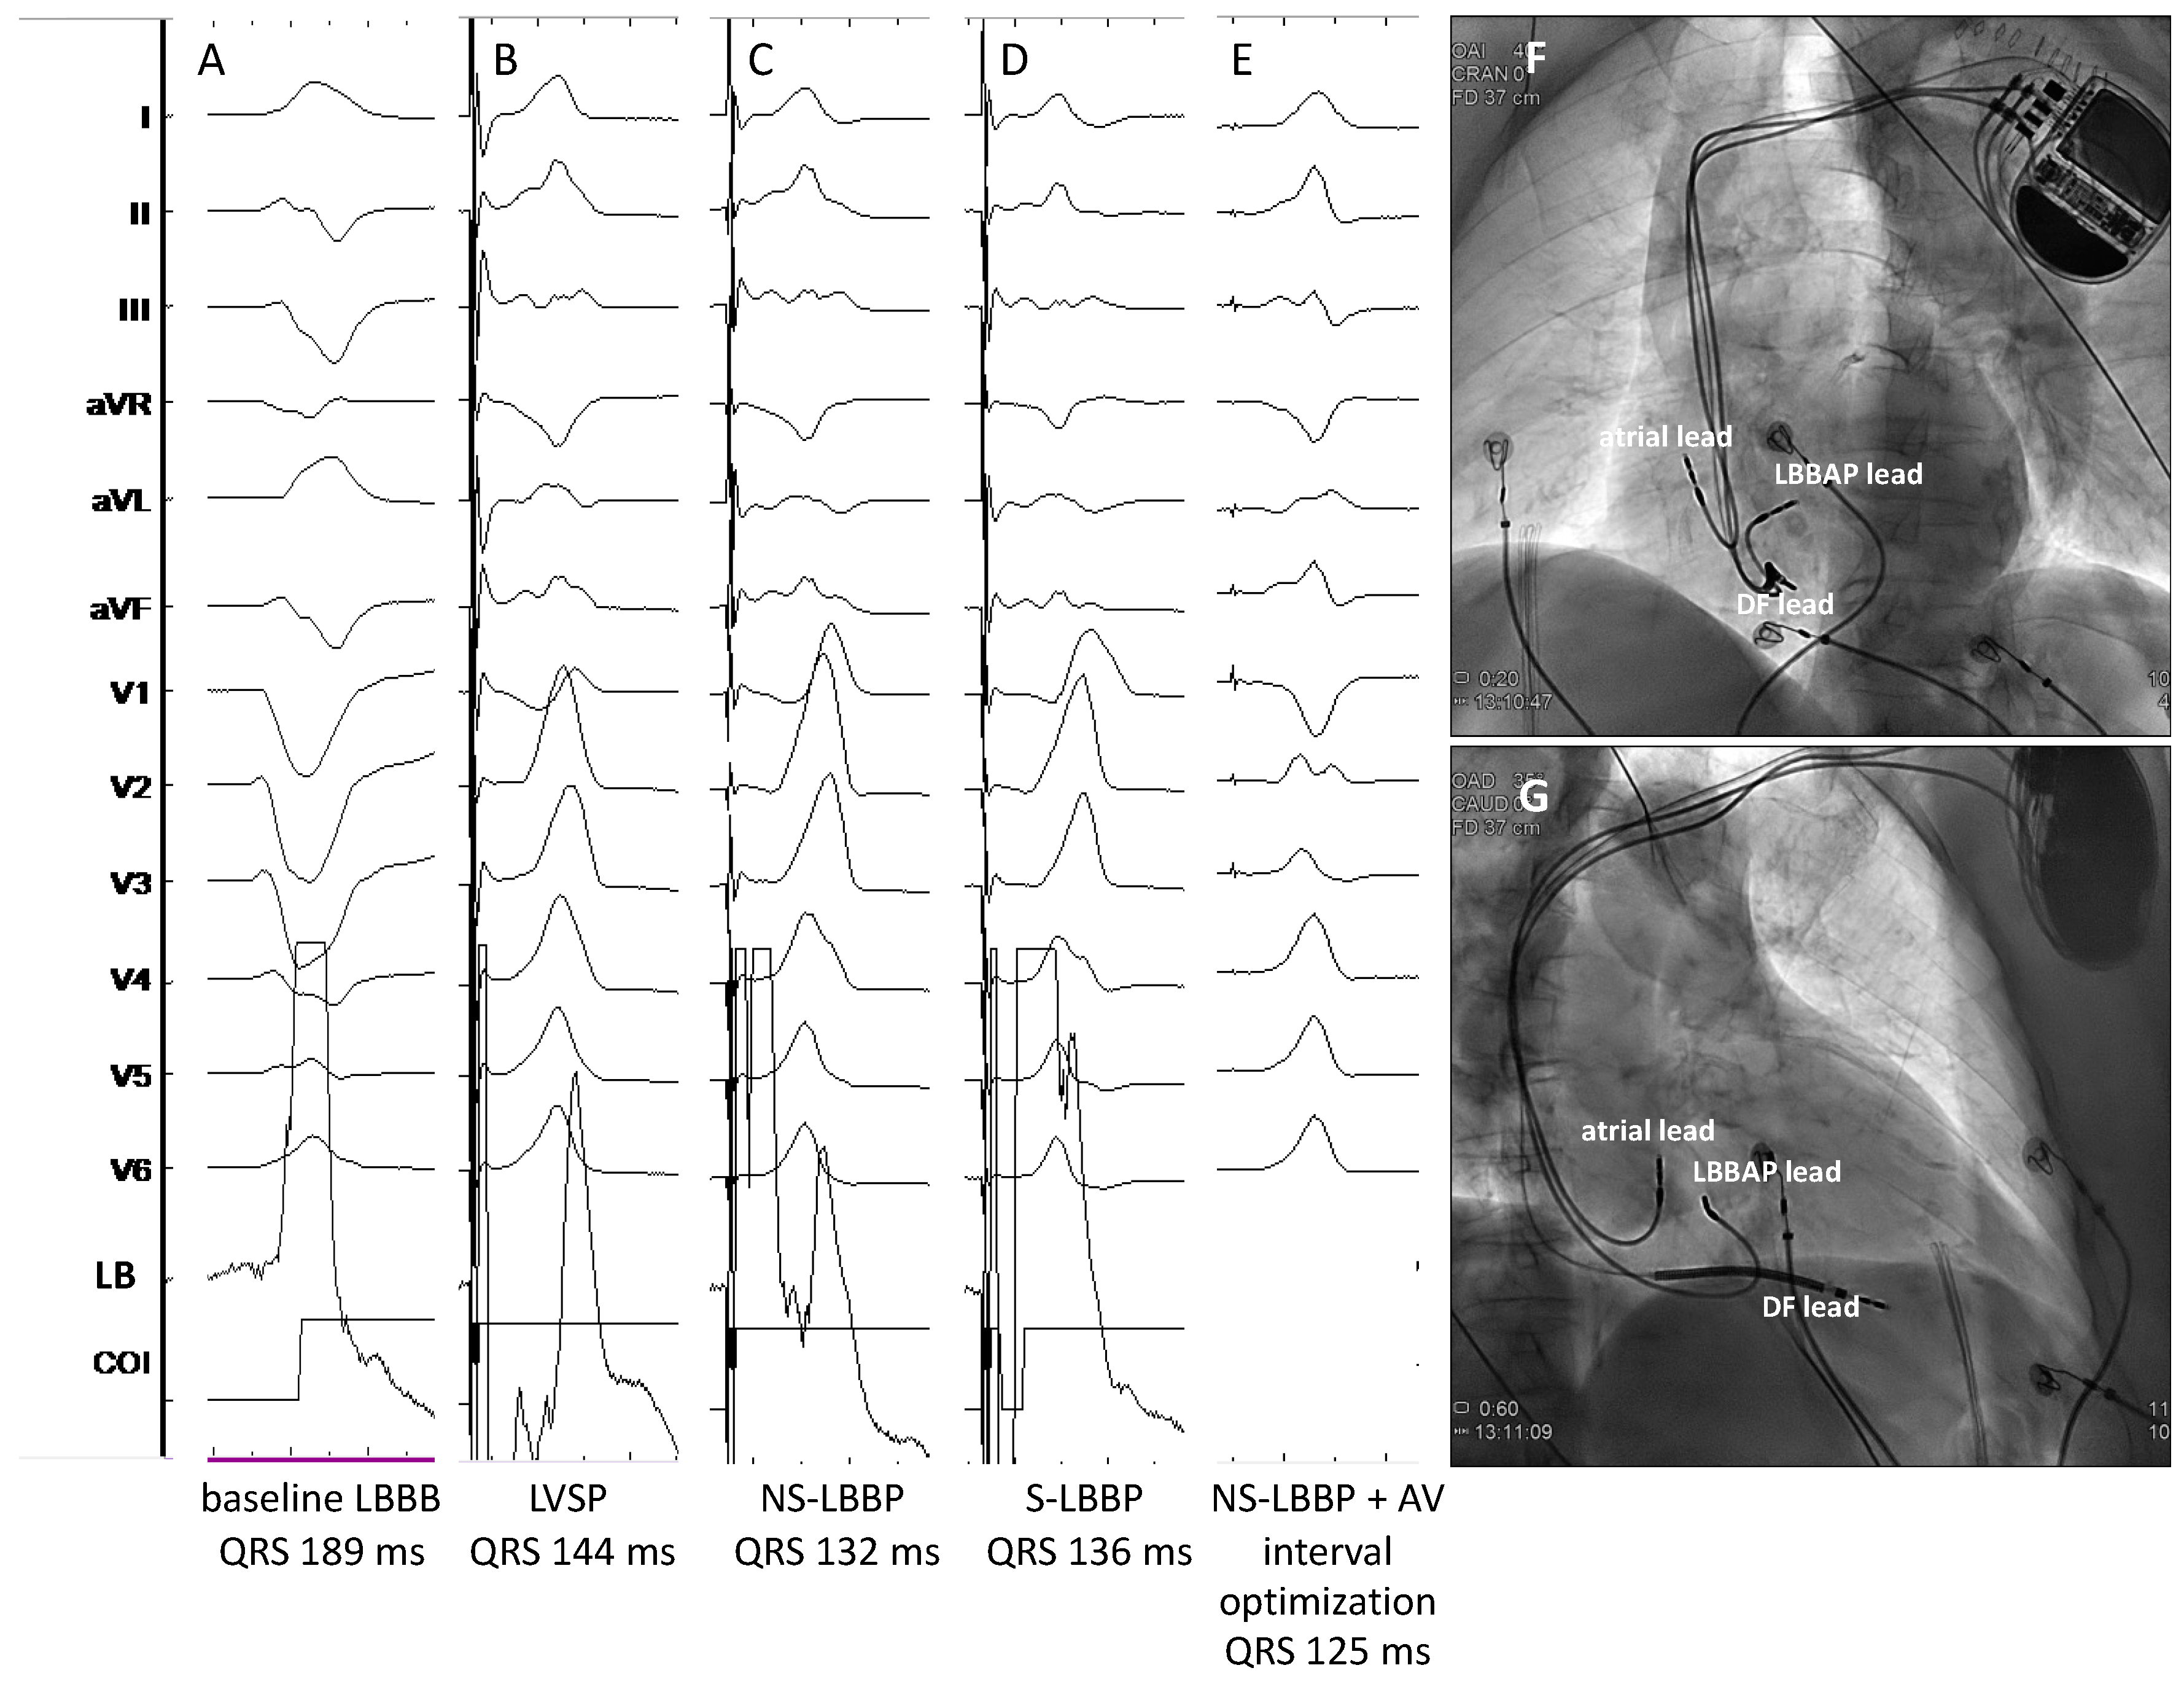

- Jastrzębski, M.; Moskal, P.; Huybrechts, W.; Curila, K.; Sreekumar, P.; Rademakers, L.M.; Ponnusamy, S.S.; Herweg, B.; Sharma, P.S.; Bednarek, A.; et al. Left bundle branch-optimized cardiac resynchronization therapy (LOT-CRT): Results from an international LBBAP collaborative study group. Heart Rhythm. 2022, 19, 13–21. [Google Scholar] [CrossRef] [PubMed]